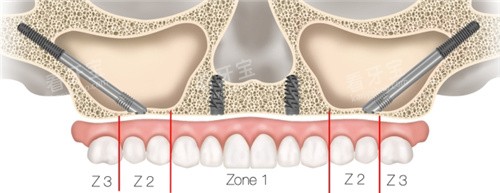

穿颧种植牙是一种将种植体穿过上颌窦底或颧骨区域,直接固定于颧骨或上颌骨的种植修复技术。与传统种植体仅植入牙槽骨不同,其核心在于利用颧骨这一人体较坚硬的骨骼(密度约为皮质骨的2倍),为种植体提供稳定的力学支撑。

颧骨位于面部两侧,呈菱形结构,骨质致密且血供丰富,抗压力强。对于上颌后牙区骨高度不足5mm的患者,传统种植体无法获得足够固位力,而穿颧种植体通过穿透上颌窦黏膜,斜向植入颧骨,可实现与天然牙相似的咀嚼功能。研究表明,穿颧种植体的10年存活率可达92%,与传统种植体相当(《口腔种植学杂志》,2023)。

?颧骨定位:通过导板引导,确保种植体与颧骨长轴呈30°-45°夹角,以获得较佳应力分布。